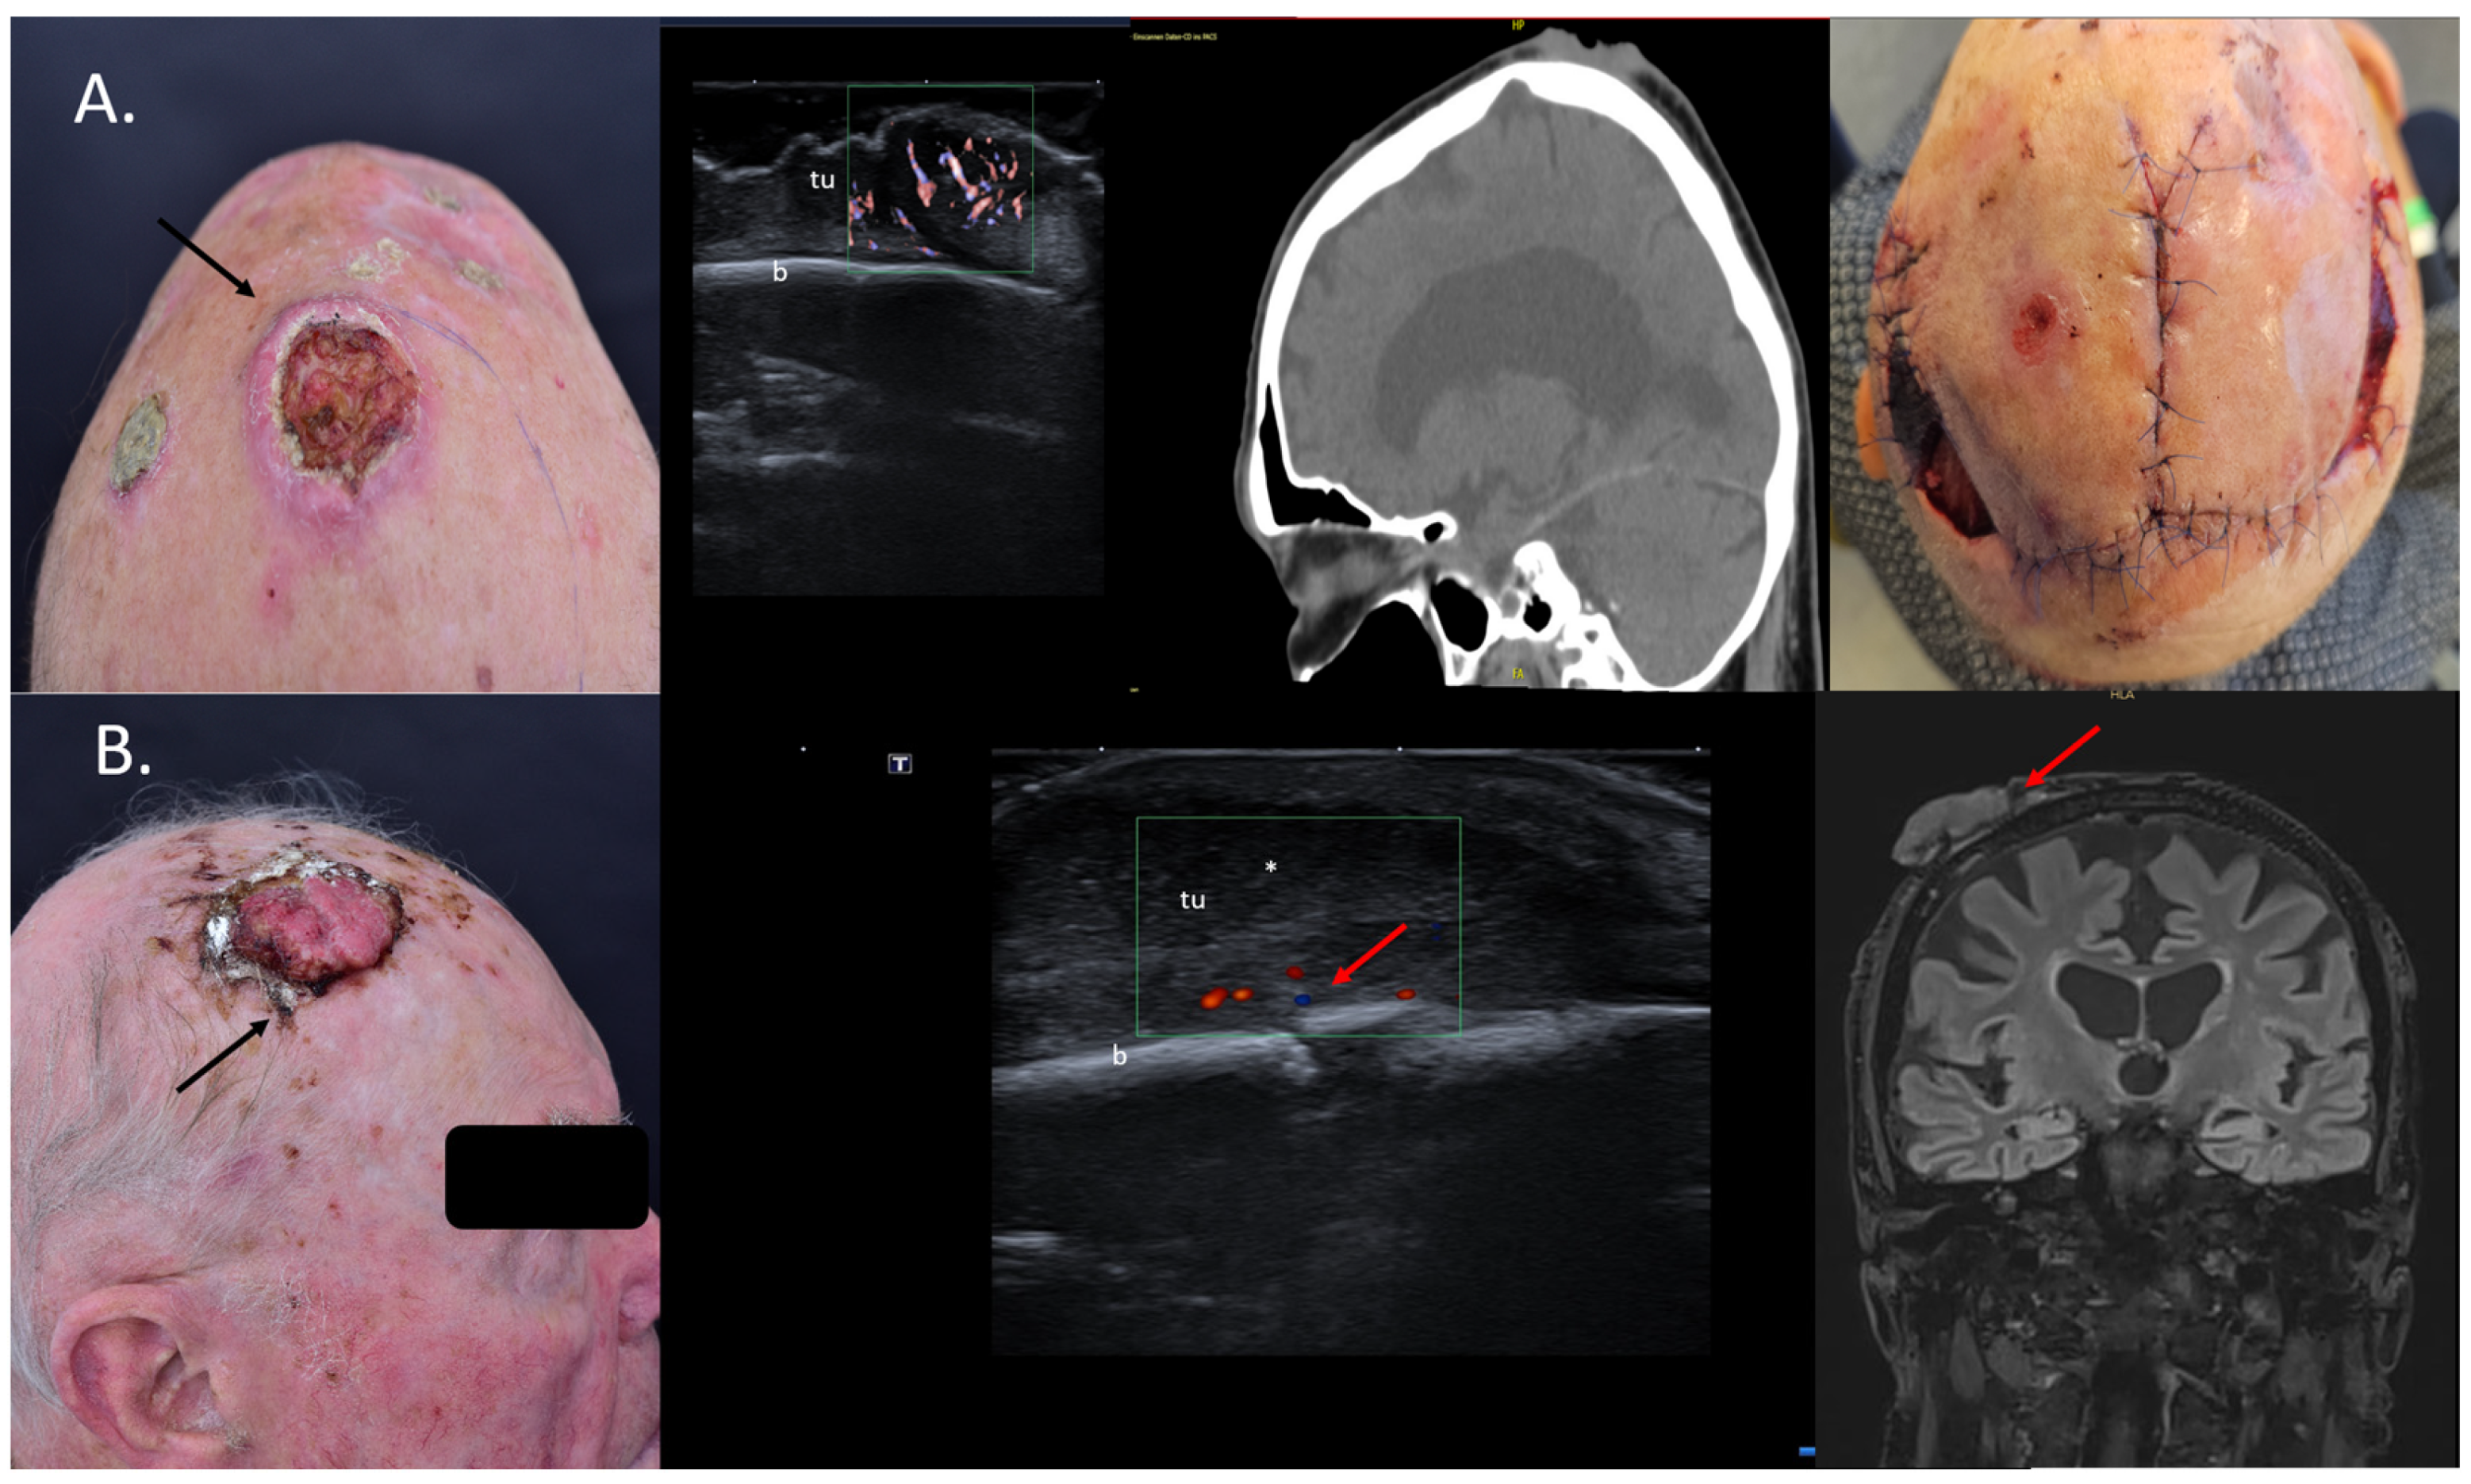

4. Assessment of the Tumor Infiltration Depth

5. Tumor Mapping and Evaluation of Operability

6. Identification of Cases for Mohs Surgery

7. Choice of Surgical Approach

10. Avoidance of Unnecessary Surgeries due to Patient Up-Staging